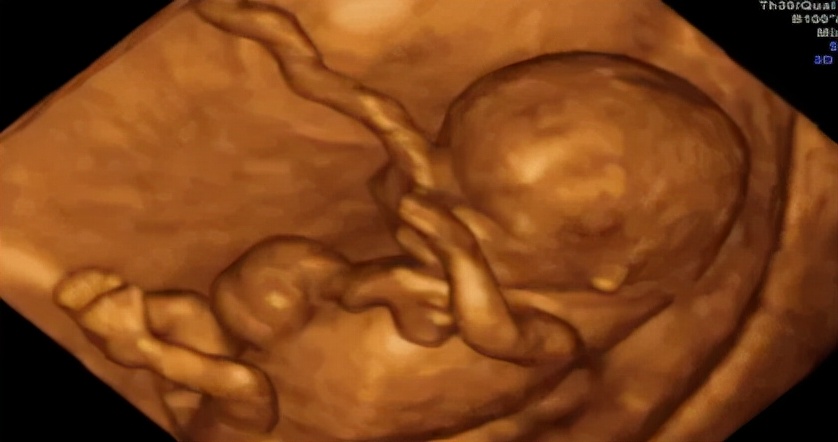

第4次(大排畸):22-24周

这个阶段是看宝宝有身体重大畸形,内脏、头、手指、四肢长骨等均需做细致检查,耗时较长。不需憋尿。这个孕周胎儿结构发育较为完善,可观察到大多数的胎儿畸形。